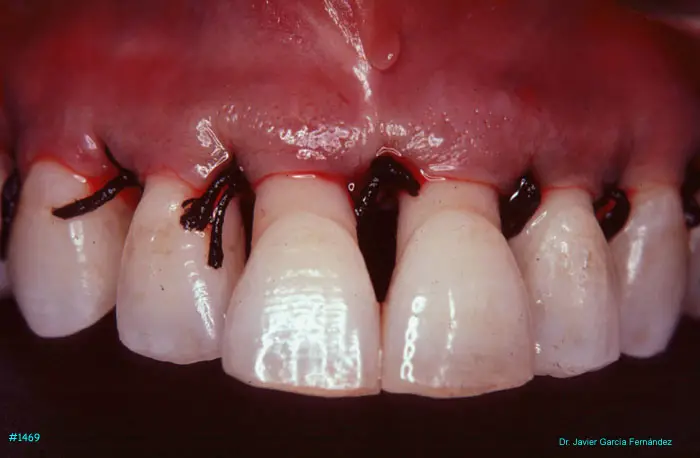

Atlas of Surgical Techniques in Periodontics. Chapter III. Atlas de Técnicas Quirúrgicas en Periodoncia